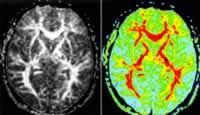

8.神經肌肉電生理改變主要表現為廣泛的神經源性損害。急性神經源性損害(失神經後2~3周)的特徵為纖顫電位正銳波束顫電位和巨大電位慢性失神經伴有再生時表現為肌肉輕收縮時運動單位動作電位時限增寬波幅明顯升高及多相波百分比上升,肌肉大力收縮時可見運動單位脫失現象。ALS的神經源性損害通常累及3個以上的區域(腦神經、頸、胸、腰骶神經支配區)。舌肌胸鎖乳突肌和膈肌也可表現為神經源性損害,後者因為在頸椎病中較少受累因而可資對兩者進行鑑別(康德暄1994)。MCV可有輕度減慢誘發電位波幅下降感覺傳導速度多正常。磁刺激運動誘發電位:經顱刺激大腦皮質運動神經元,並在相應的肌肉記錄到動作電位該方法可測定中樞運動傳導時間,對確定皮質脊髓束的損害具有重要價值。肌肉活檢對ALS的診斷並不是必要的,但在一些情況下有助於鑑別神經源性肌萎縮。

要早期診斷肌萎縮側索硬化,除了神經科臨床檢查外,還需做肌電圖、神經傳導速度檢測、血清特殊抗體檢查、腰穿腦脊液檢查、影像學檢查,甚至肌肉活檢。鑑別診斷